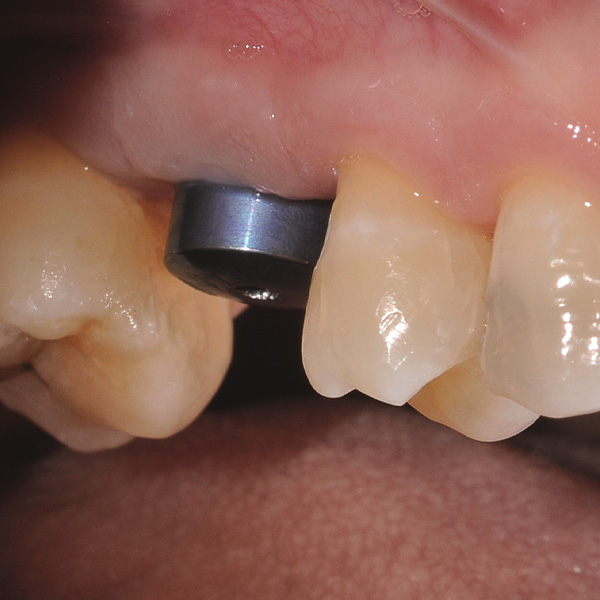

Restorations and implants are exposed to especially high loads. After extraction and implantation, the patient lacks the elastic fiber apparatus of the natural dental bed. As a result, chewing forces are not absorbed, but transmitted directly to the restoration, the implant, the bone and the opposing dentition. The hybrid ceramic VITA ENAMIC provides a dual network structure of ceramic (86 wt%) and polymer (14 wt%). This results in a dentin-like elasticity and the ability to absorb chewing forces. Due to its high vertical dimension, the polychrome blank VITA ENAMIC multiColor in the EMC-16 geometry enables the production of one-piece, monolithic abutment crowns, even with atrophied bone. In the following article, dentist Professor Dr. Alexander Hassel demonstrates how he provides a patient with this type of restoration.